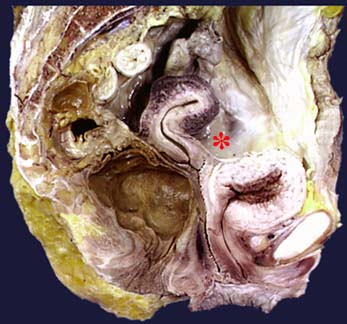

Uterus

Uterus - body

Uterus - cervical canal

Uterus - cervix

Uterus - cervix, intravaginal part

Uterus - external os

Uterus - fundus

Uterus - isthmus

Uterus - uterine cavity

Vagina

Vagina - fornix

Vesicouterine pouch

Uterine tube - ampulla

Uterine tube - fimbriae

Uterine tube - infundibulum

Uterine tube - isthmus

Uterine tube - ostium

Ovary

Ovarian ligament

Suspensory ligament of ovary